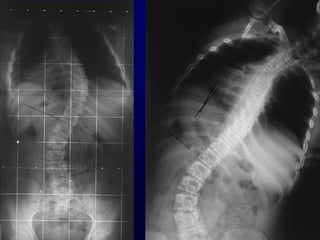

X-Rays

• Αηηημιμγία θαη ηύπμξ ηεξ παναμόνθςζεξ.

• Γκηόπηζε, έθηαζε θαη εοθαμρία ημο θονηώμαημξ.

• ΢οκμδέξ ζογγεκείξ παναμμνθώζεηξ

• ΢θειεηηθή ςνίμακζε.

Σμ πηό πμιύηημμ δηαγκςζηηθό ενγαιείμ.

AP

Απόζηαζε 2 m

Films: 36 x 91 cm

36 x 43 cm

Σ1 - S1

Ημνμόξ: Χςνίξ ζηνμθή

Δηόνζςζε ακηζμζθειίαξ

LATERAL

Ηάμρε ώμςκ 90°

Ιεηνηθό ζθάιμα + - 5º